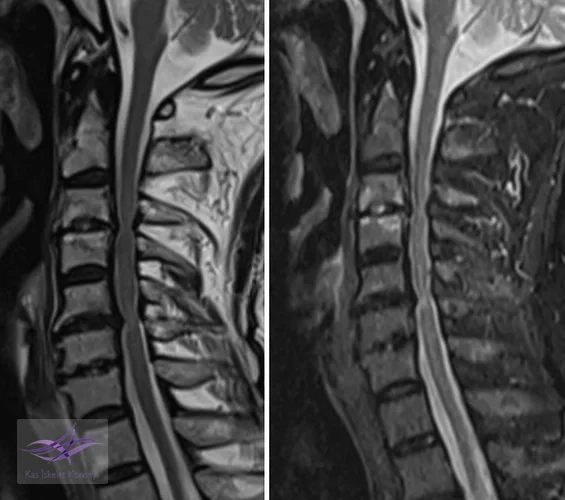

İncelemeler: Servikal MRG'de dar kanal saptandı, kanal ön-arka çapı 5 mm'nin altına inmişti.

Resim 1. Preop MRG incelemelerinde servikal dar kanal ve omurilikte myelopatik değişiklikler görülmekte.